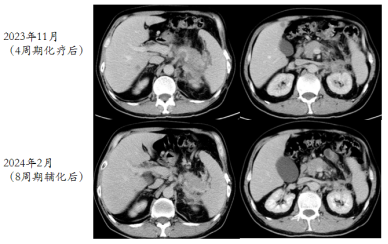

2023-08-29胸部CT未见转移,腹部CT:结肠脾曲术后,肝多发转移,胰腺区,肾前,脾内侧多发转移,病变包绕胰腺及脾动脉静脉,胃底及左上腹静脉迂曲扩张,肝门区,肠系膜内及腹膜后,左侧髂血管旁周围多发肿大淋巴结。左肾周受侵。

image.png

图1 2023年8月29日检查结果

2023-09-01开始一线达拉非尼+西妥昔单抗+FOLFIRI*8cs。

(2023年11月)4周期化疗后,复查CT评效:肝多发转移,较前减少缩小,胰腺区,左肾前,脾内侧多发转移较前明显缩小,肝门区,肠系膜内及腹膜后淋巴结较前明显缩小,部分消失。评效部分缓解(PR)。

图2 4周期化疗后复查CT结果

(2024年02月)8周期化疗后,复查CT评效:肝多发转移,较前减少缩小,胰腺区,左肾前,脾内侧多发转移较前稍缩小,肝门区,肠系膜内及腹膜后淋巴结较前明显缩小,部分消失。评效维持PR。

图3 8周期化疗后复查CT结果